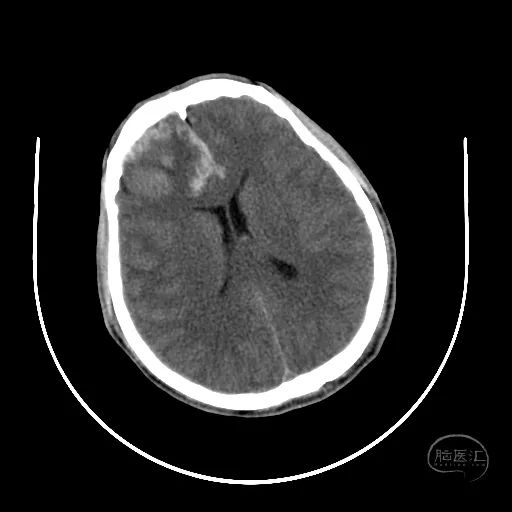

2小时后复查颅脑CT显示第四脑室受压消失。

小脑挫伤灶水肿较前加重,脑干及小脑半球低密度改变。

硬膜外血肿无明显变化。

右额叶脑挫裂伤并脑内血肿形成,中线结构明显移位。

左侧脑室有扩张表现。

此时患者双侧瞳孔散大,GCS评分4分,气管插管,自主呼吸。家属同意手术治疗。

幕上脑疝,幕下压力也高,第四脑室闭塞,导水管显示不清,脑室有扩张表现。